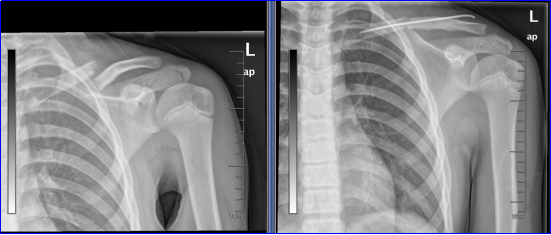

近日,河南省胸科医院骨科接诊了一位年仅9岁的特殊骨折患者。这名小患者是一名自由式滑雪运动员,在训练中意外摔倒,导致左侧锁骨中段骨折。作为曾经在全国比赛中荣获银牌的青少年组选手,其治疗不仅需要修复骨骼,更需兼顾运动功能的恢复与未来的成长发育空间。

面对这样一位处于生长发育期的小运动员,河南省胸科医院骨科副主任(主持工作)张春雷与团队经过慎重评估,最终选择了“闭合复位弹性髓内针内固定术”这一微创方案。

手术仅通过两个约5毫米的微小切口,将一根柔韧的钛合金针植入骨髓腔内,从内部实现对骨折端的稳定支撑。这种方法创伤小、出血少,且避免了传统钢板对骨膜血运的破坏,有利于骨骼愈合。更关键的是,弹性固定方式允许骨折处在可控范围内微动,符合生理愈合机制,同时不影响锁骨生长板的正常发育,为患儿今后的运动生涯保留了更多可能。

手术在C臂机的精准引导下顺利进行,仅用时45分钟。术后第三天,患儿恢复平稳,已顺利出院,为后续的康复训练争取了宝贵时间。这一治疗过程的背后,体现了运动医学与创伤骨科相结合的诊疗思路——不仅关注如何治好伤,更关注如何让患者安全地重返运动。